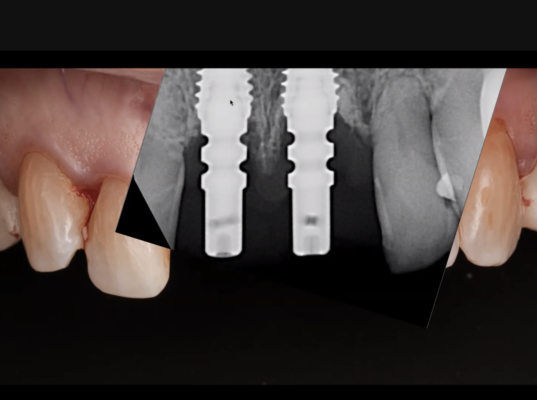

What would u do? Pt was getting headaches bc she was hitting too hard on LL didnt tell me till she rolls in for suture removal and out implant comes. My current plan is replace and sleep it. Concerned about LR also, will flap and visualize possibly replace also.